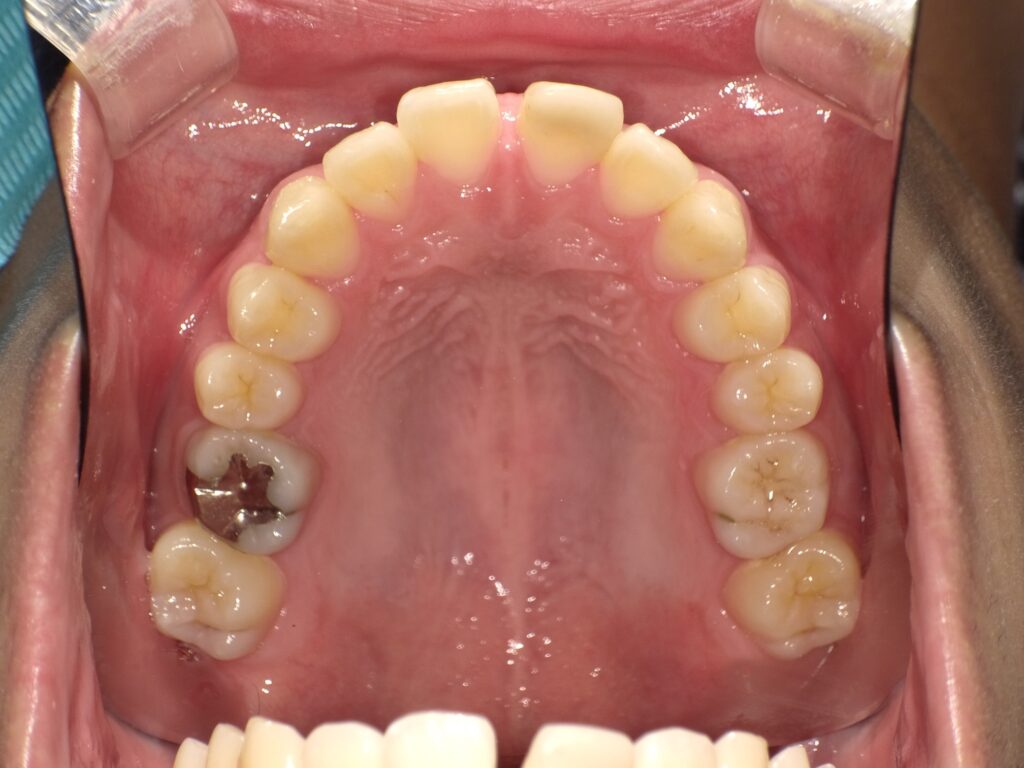

• 【治療前】

隙間がきれいに閉じ、自然な歯並びになっているのが分かります。